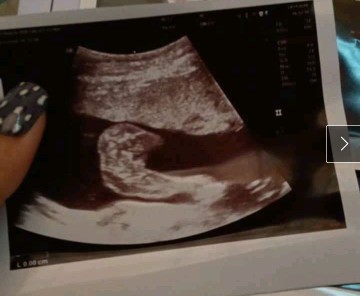

โชว์ผลซาวด์กันค่ะ

คุณลุงหมอบอกมีกลีบ?ใครมีกลีบ ใครมีแท่ง ลงมาอวดกันจร้า

ดูยังไงก็ดูไม่ออกค่ะ